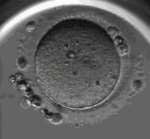

三代试管技术的成功率因多种因素而异,包括年龄、女性卵巢储备情况、男性精子质量等。据统计,40岁以下的女性进行三代试管的成功率约为50%-70%,而40岁以上女性的成功率则会明显下降。